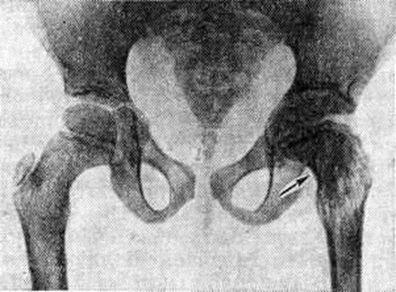

Рис. 2.

Рентгенограмма коленного сустава ребёнка 4 лет, больного эпифизарным остеомиелитом: эпифиз и метафиз бедренной кости частично разрушены (указано стрелками); бедренная кость деформирована, в том числе вследствие поражения зоны роста.